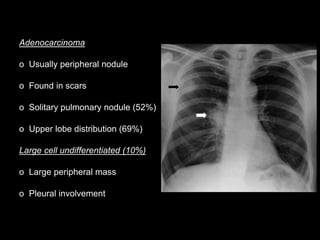

Adenocarcinoma

o Usually peripheral nodule

o Found in scars

o Solitary pulmonary nodule (52%)

o Upper lobe distribution (69%)

Large cell undifferentiated (10%)

o Large peripheral mass

o Pleural involvement